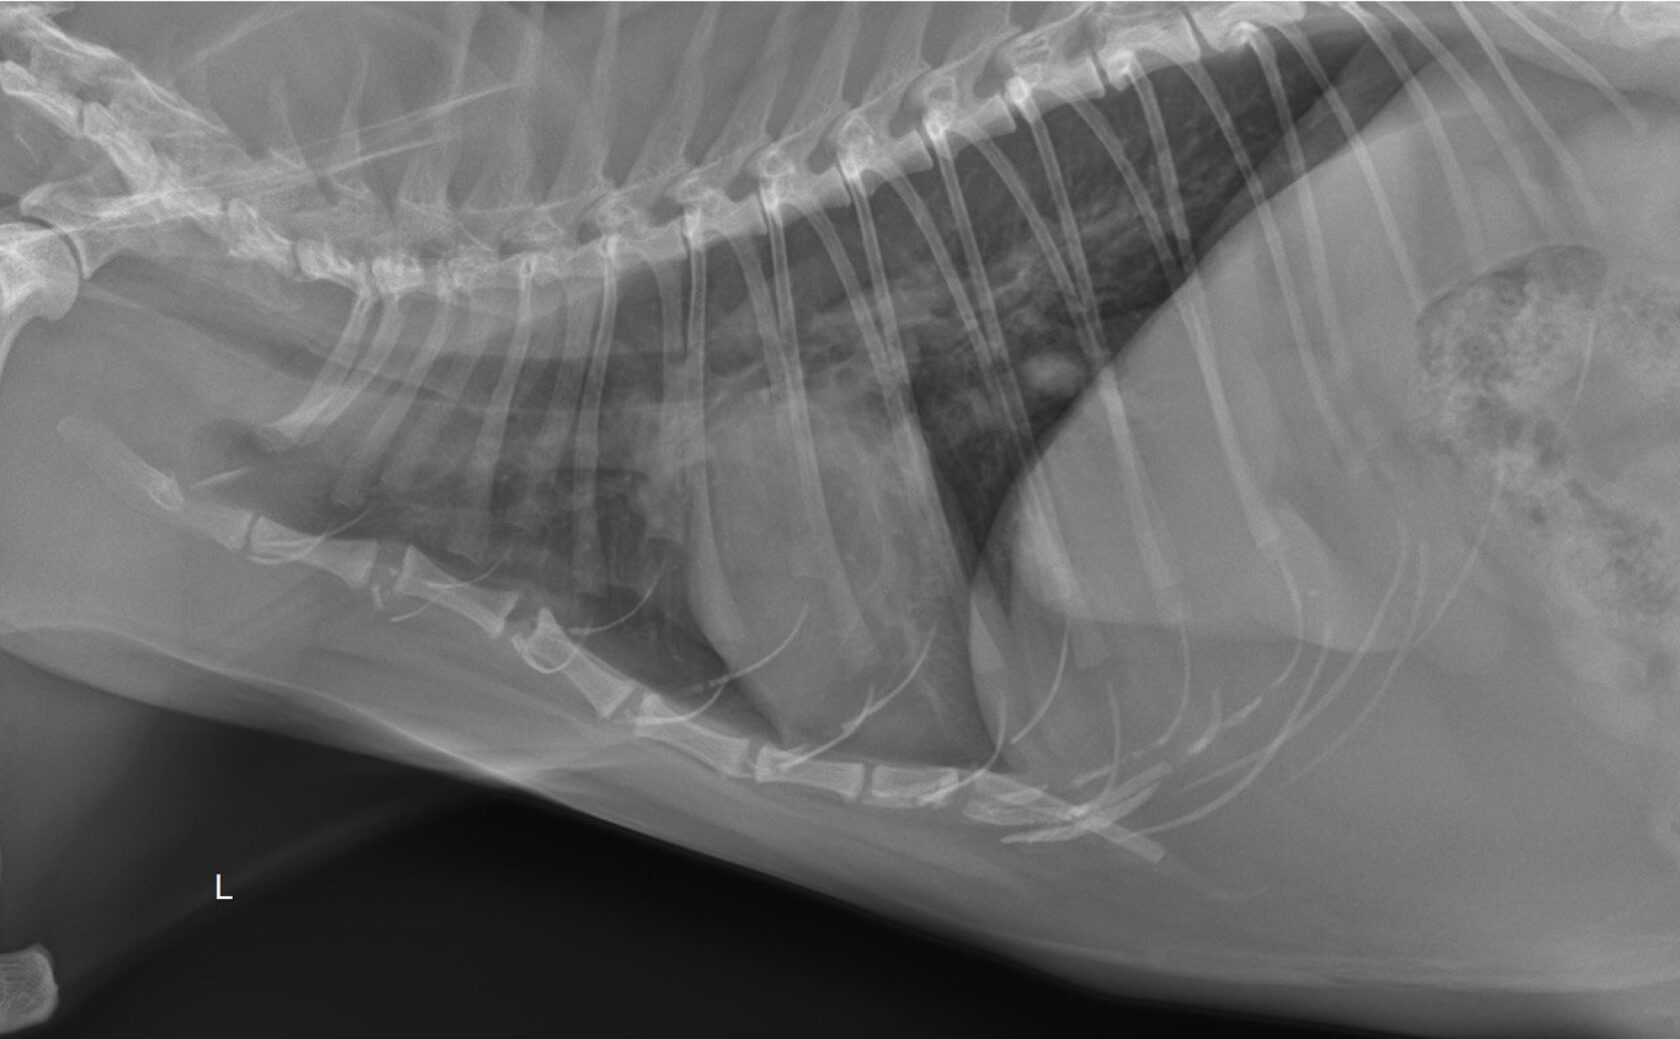

- направления на проведение рентгенографии с заключением рентгенолога (необходимо сделать 3 проекции, рентген в одной проекции не информативен).